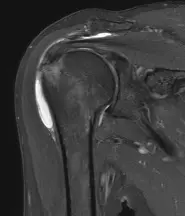

Abbildung: Ausgeprägte Bursitis (weiße Fläche) bei chronischem Impingement- Syndrom in der Magnetresonanztherapie

- Bildgebung: Ultraschall, Röntgen (Knochenveränderungen), MRT (zum Ausschluss von Sehnenschäden)